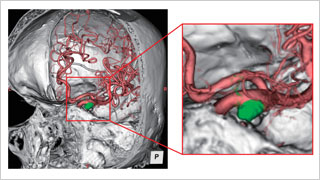

日本医科大学 脑神经外科,博慈会纪念综合医院 脑神经外科

佐藤 俊